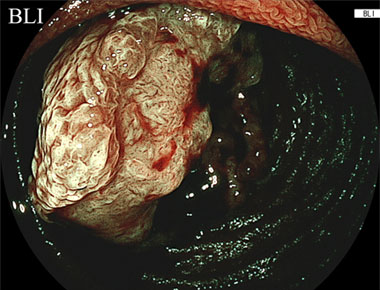

2024年5月に発売された新型ダブルバルーン内視鏡 EN-840Tは高解像度CMOSセンサーを搭載することで、従来機種と比較し高解像度の内視鏡画像の撮影を可能にし、さらにBLI (blue laser imaging)やLCI (linked color imaging)といった画像強調内視鏡観察により病変の視認性向上が期待されます。また、同時にLED光源搭載内視鏡システムの新モデル「ELUXEO 8000システム」を導入し血液の色の濃淡や微妙な色の違いを強調し、出血時の出血点検出のサポートが期待されるACI (amber color imaging)も使用可能です。さらにEN-840Tは高弾発グラデーション軟性部を採用し、従来機種と同等の先端部径、鉗子口径を維持し従来機種と比較し挿入性・操作性がさらに向上することが期待されます。

またこちらは原発性小腸がんの症例ですが、白色光観察と比較すると、LCIでは病変の発赤がより明瞭かし、BLI観察では病変内部の不正な表面構造、血管構造がより明瞭に肝観察できることがおわかりいただけるかと思います。